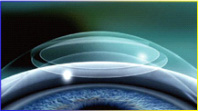

手术微创、无瓣,安全性更高全飞秒切口仅为2-4mm,保存了角膜的完整性,减少对角膜神经纤维的损伤,提高视觉弧,排除了以往制瓣类激光手术的术后隐患。

小光斑,术后视力更稳定光斑越小,切削越有效,且对角膜组织的破坏越小。切削的角膜基质面光滑,术后视力更稳定。

弧形压平技术,术中舒适度更好接触眼球的镜面经独特设计,规格多种,适应不同大小的眼睛,压平为弧形镜,更符合角膜生理状态,术中舒适度更好。

负压低,患者更易配合负压是手术过程中,负压环对眼球产生的压力。负压高,会导致眼压升高,视神经和视网膜受到压迫,术中出现短暂的黑朦情况,患者一着急眨眼,会导致负压环脱落,手术被迫中断。而全飞秒负压极低,术中不会出现眼压升高,患者容易配合。

1、飞秒激光制作微透镜下层

1、飞秒激光制作微透镜下层 2、飞秒激光制作透镜上层

2、飞秒激光制作透镜上层 3、飞秒激光制作微切口

3、飞秒激光制作微切口 4、取出微透镜完成手术